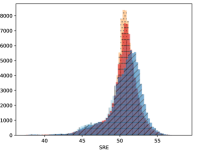

To visualise similarity metrics that compare image pairs (RMSE, SRE, SSIM) two metric distributions are generated: intra-similarity and inter-similarity. For each compared sample 300 random images are selected. The inter-similarity distribution is calculated for each image pair combination from both compared samples e.g. generated images of COVID-19 and real images of COVID-19. For the intra-similarity, all pairs of images in a single sample e.g real images of COVID-19 are considered. By comparing the shape of intra-similarity for the training subsample (Dataset) with the inter-similarity of training and generated samples the quality of the generated sample can be judged. It is also possible to compare in this way between the four image classes present in the dataset. The resulting distributions of inter-similarity of COVID-19 and the three remaining classes are compared in Fig. 4 to distributions of intra-similarity of the COVID-19 sample for each metric. All metrics, as expected based on available medical evidence Rubin et al. (2020), indicate that there are visible differences not only between COVID-19 and normal samples but also between viral pneumonia and lung opacity. Therefore, all classes should be distinguishable.

To visualise differences between synthetic and real samples distributions are generated for each of the RMSE, SRE and SSIM metrics: intra-similarity and inter-similarity. For each compared sample 300 random images are selected. The inter-similarity distribution is calculated for each image pair combination from both compared samples e.g. generated images of COVID-19 and real images of COVID-19. For the intra-similarity, all pairs of images in a single sample e.g real images of COVID-19 are considered. The distributions for generated samples describe very well the distributions for corresponding real images as shown in Fig. 6.